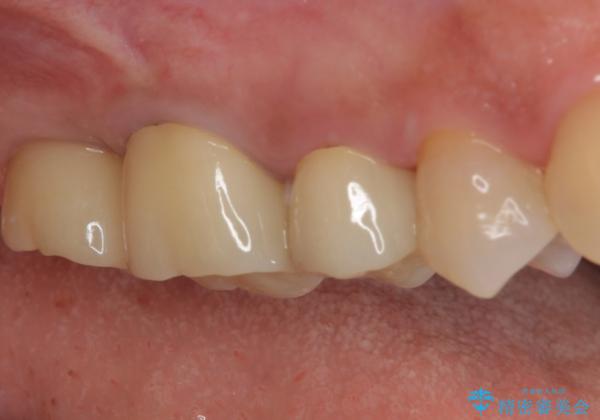

右上の一番奥の歯が欠損しており、その手前の歯2つを土台に連結されたクラウンが装着されていました。

不安定な咬み合わせとなっており、クラウンの表面が剥離していたため、インプラントによる欠損補綴治療を行い、手前2つの歯も一緒に補綴治療を行うこととしました。